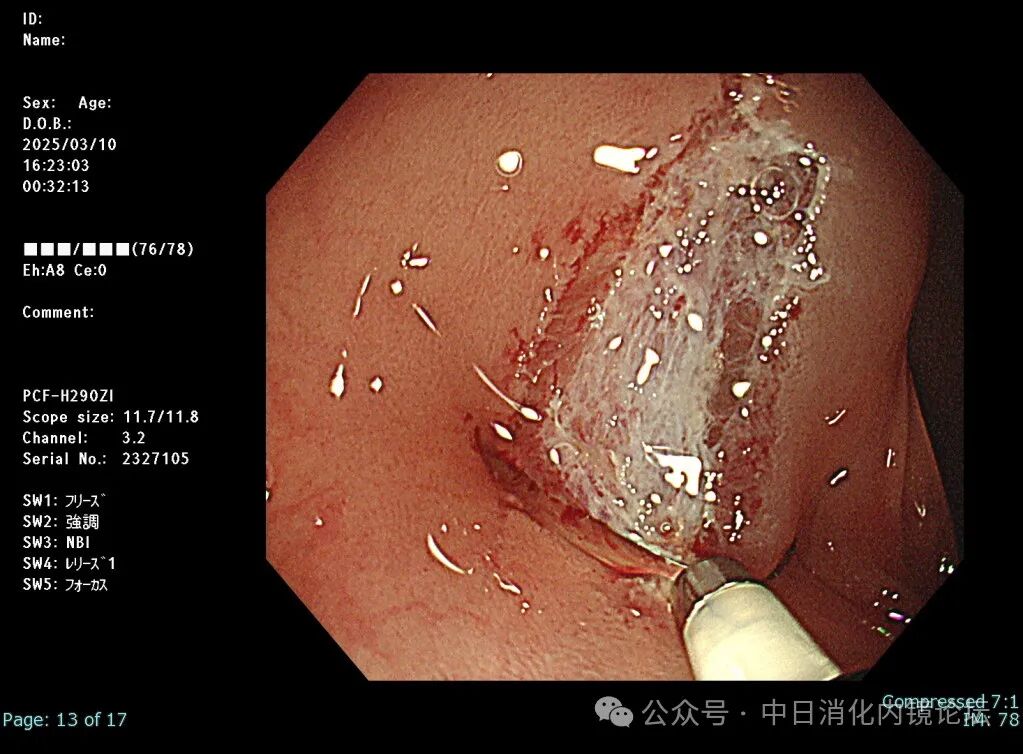

在繁忙的临床工作中按照日本消化内镜学会倡导的病变观察流程,便可事半功倍,极大地提高诊断准确性和检查效率。病变观察远景→近景→放大,白光→NBIJNET→靛胭脂 pit pattern。切除后创面确认,确保无残留,断端阴性→肛侧腹侧点墨标记→标本固定,为病理诊断以及今后可能的追加治疗提供完整精确的原始资料。